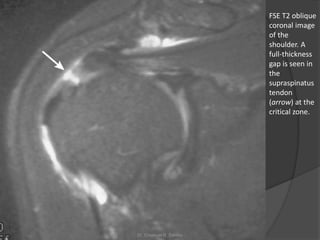

FSE T2 oblique

coronal image

of the

shoulder. A

full-thickness

gap is seen in

the

supraspinatus

tendon

(arrow) at the

critical zone.

FSE T2 oblique coronalimage of the shoulder. A full-thickness gap is seen in the supraspinatus tendon (arrow) at the critical zone. Dr. Emanuel R. Dantas